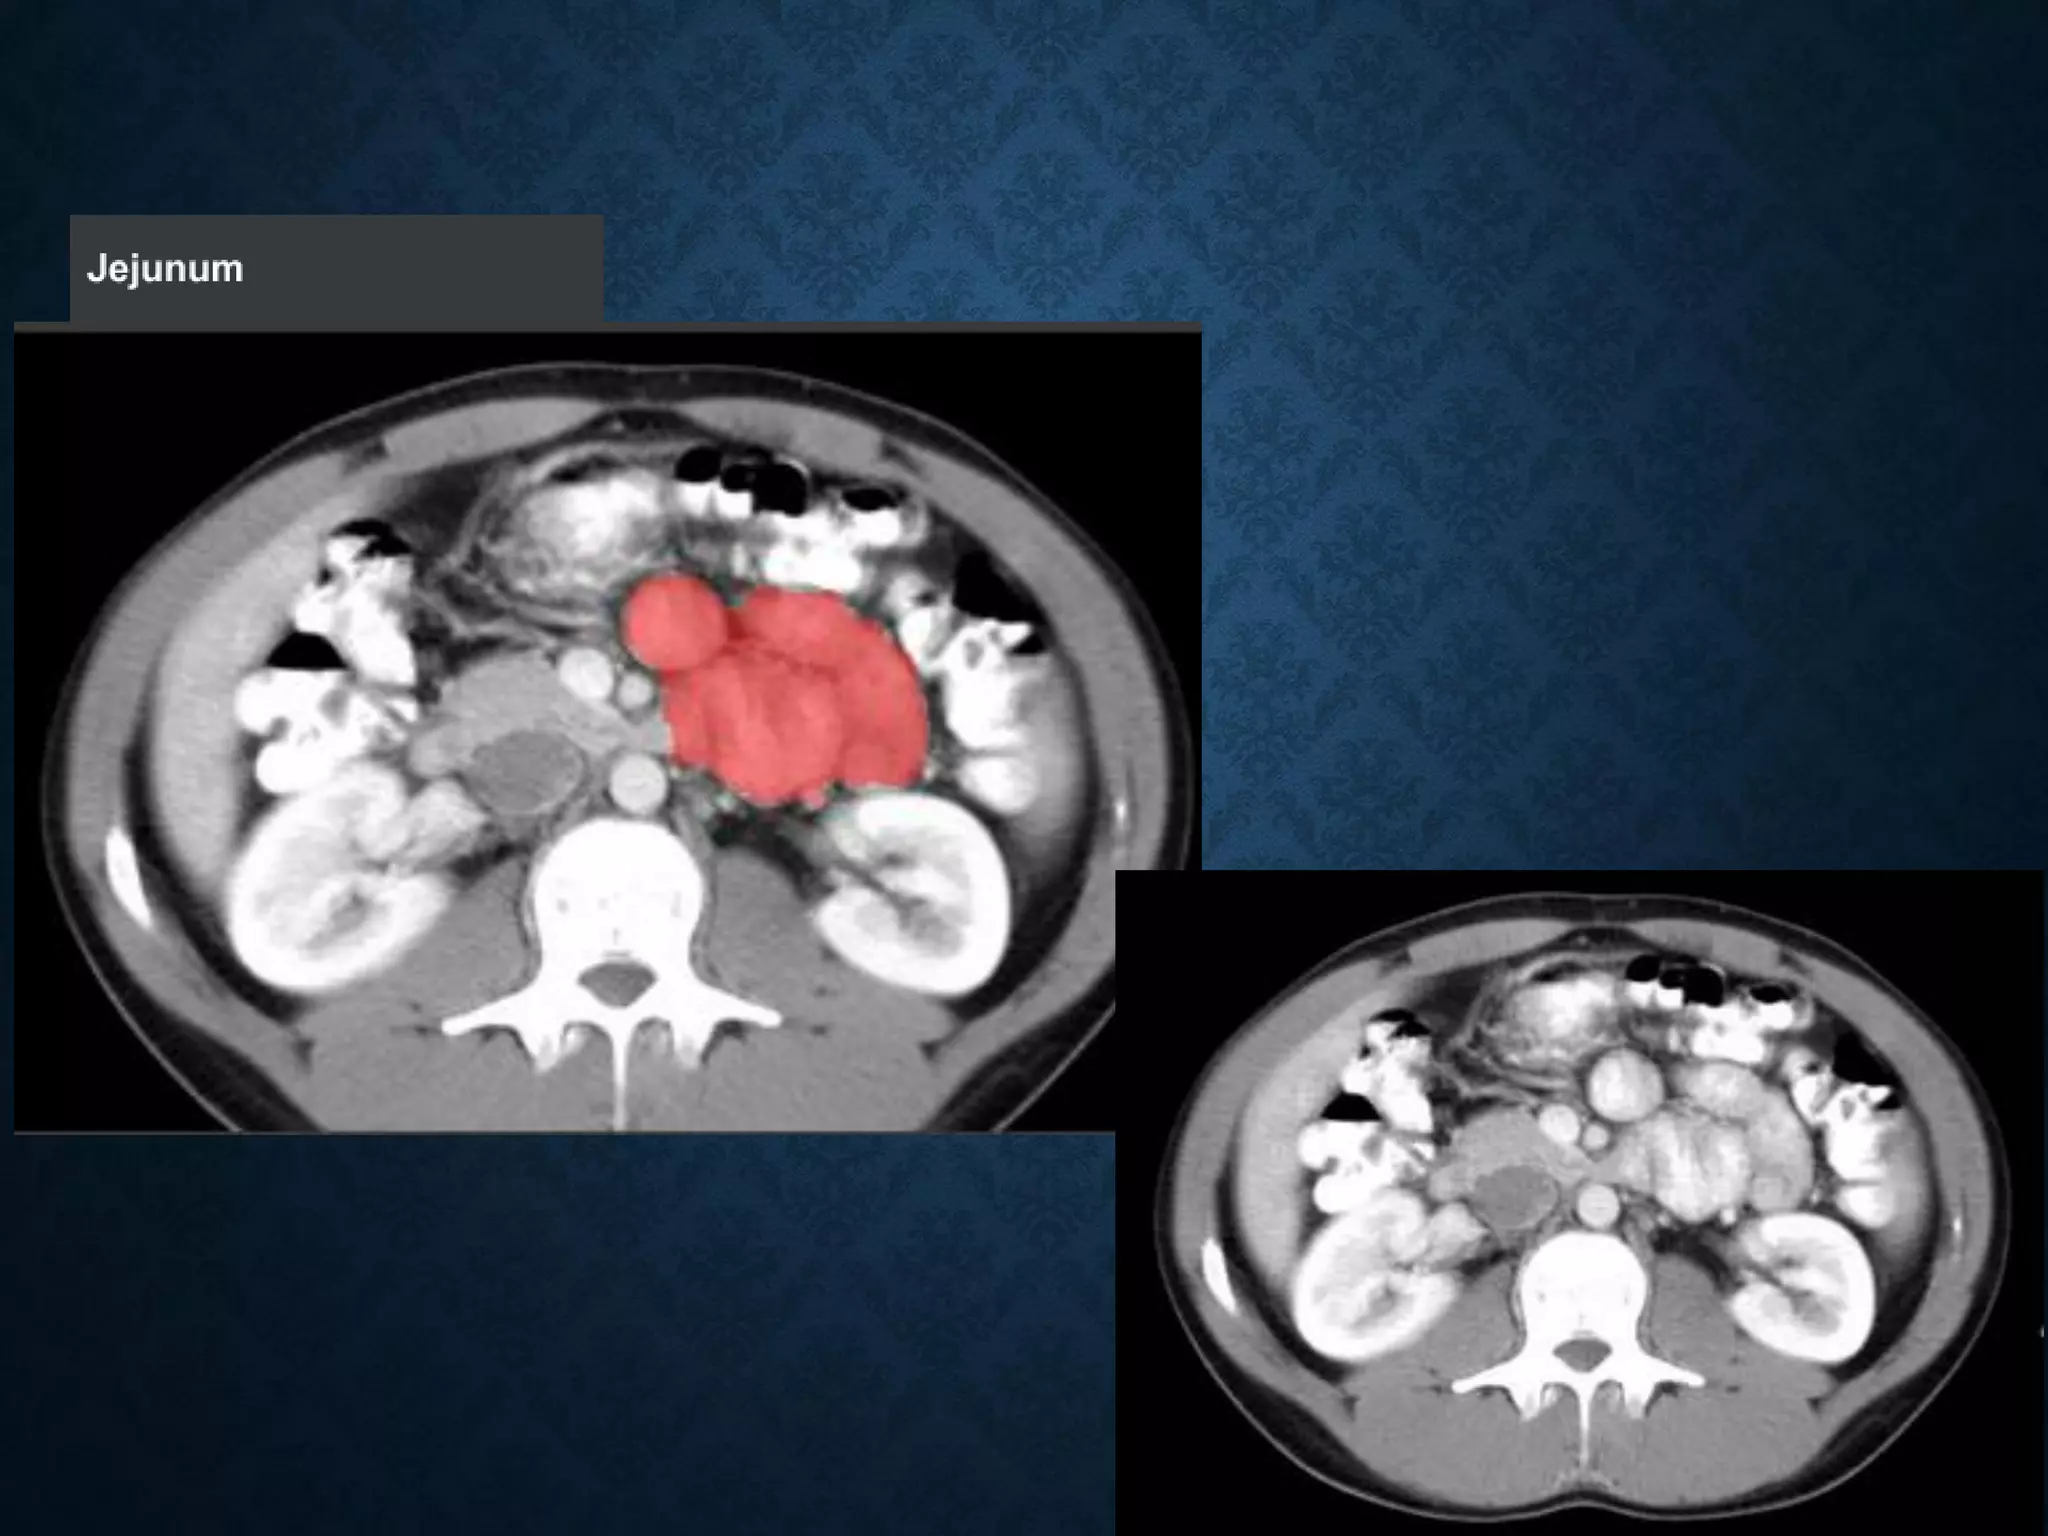

SUPERIOR MESENTERIC VEIN

• In anatomy, the superior mesenteric vein (SMV) is a blood vessel

that drains blood from the small intestine (jejunum and ileum).

SUPERIOR MESENTERIC VEIN •In anatomy, the superior mesenteric vein (SMV) is a blood vessel that drains blood from the small intestine (jejunum and ileum). • At its termination behind the neck of the pancreas, • the SMV combines with the splenic vein to form the hepatic portal vein. • The SMV lies to the right of the similarly named artery, the superior mesenteric artery, which originates from the abdominal aorta.